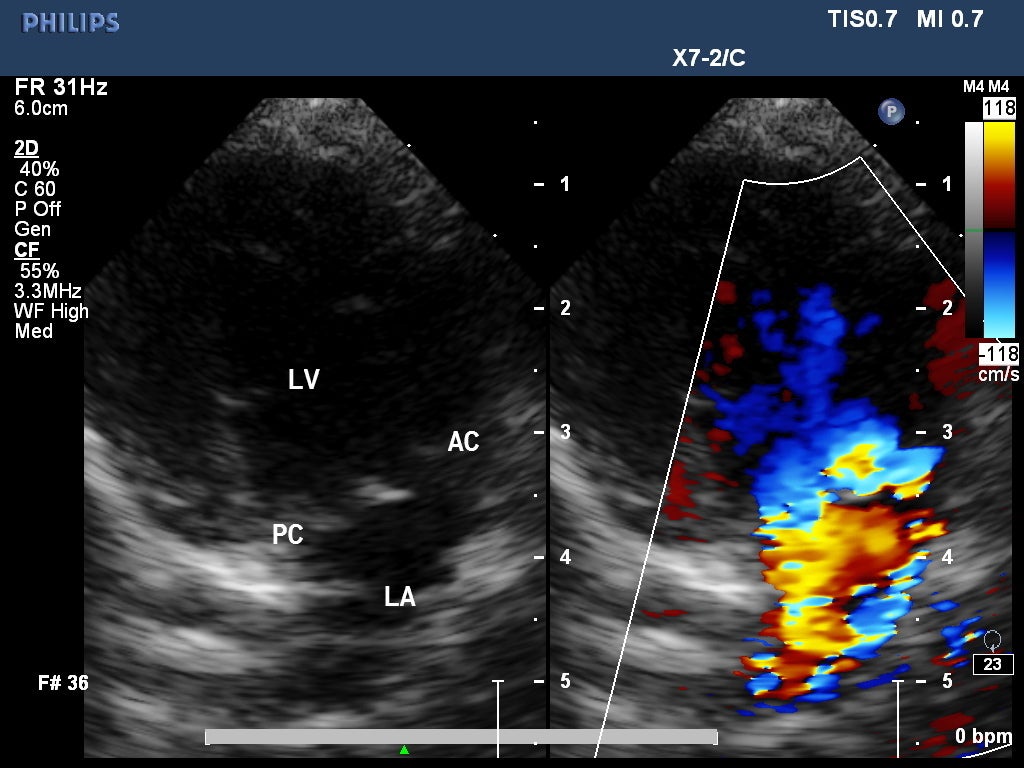

血液が逆流している様子